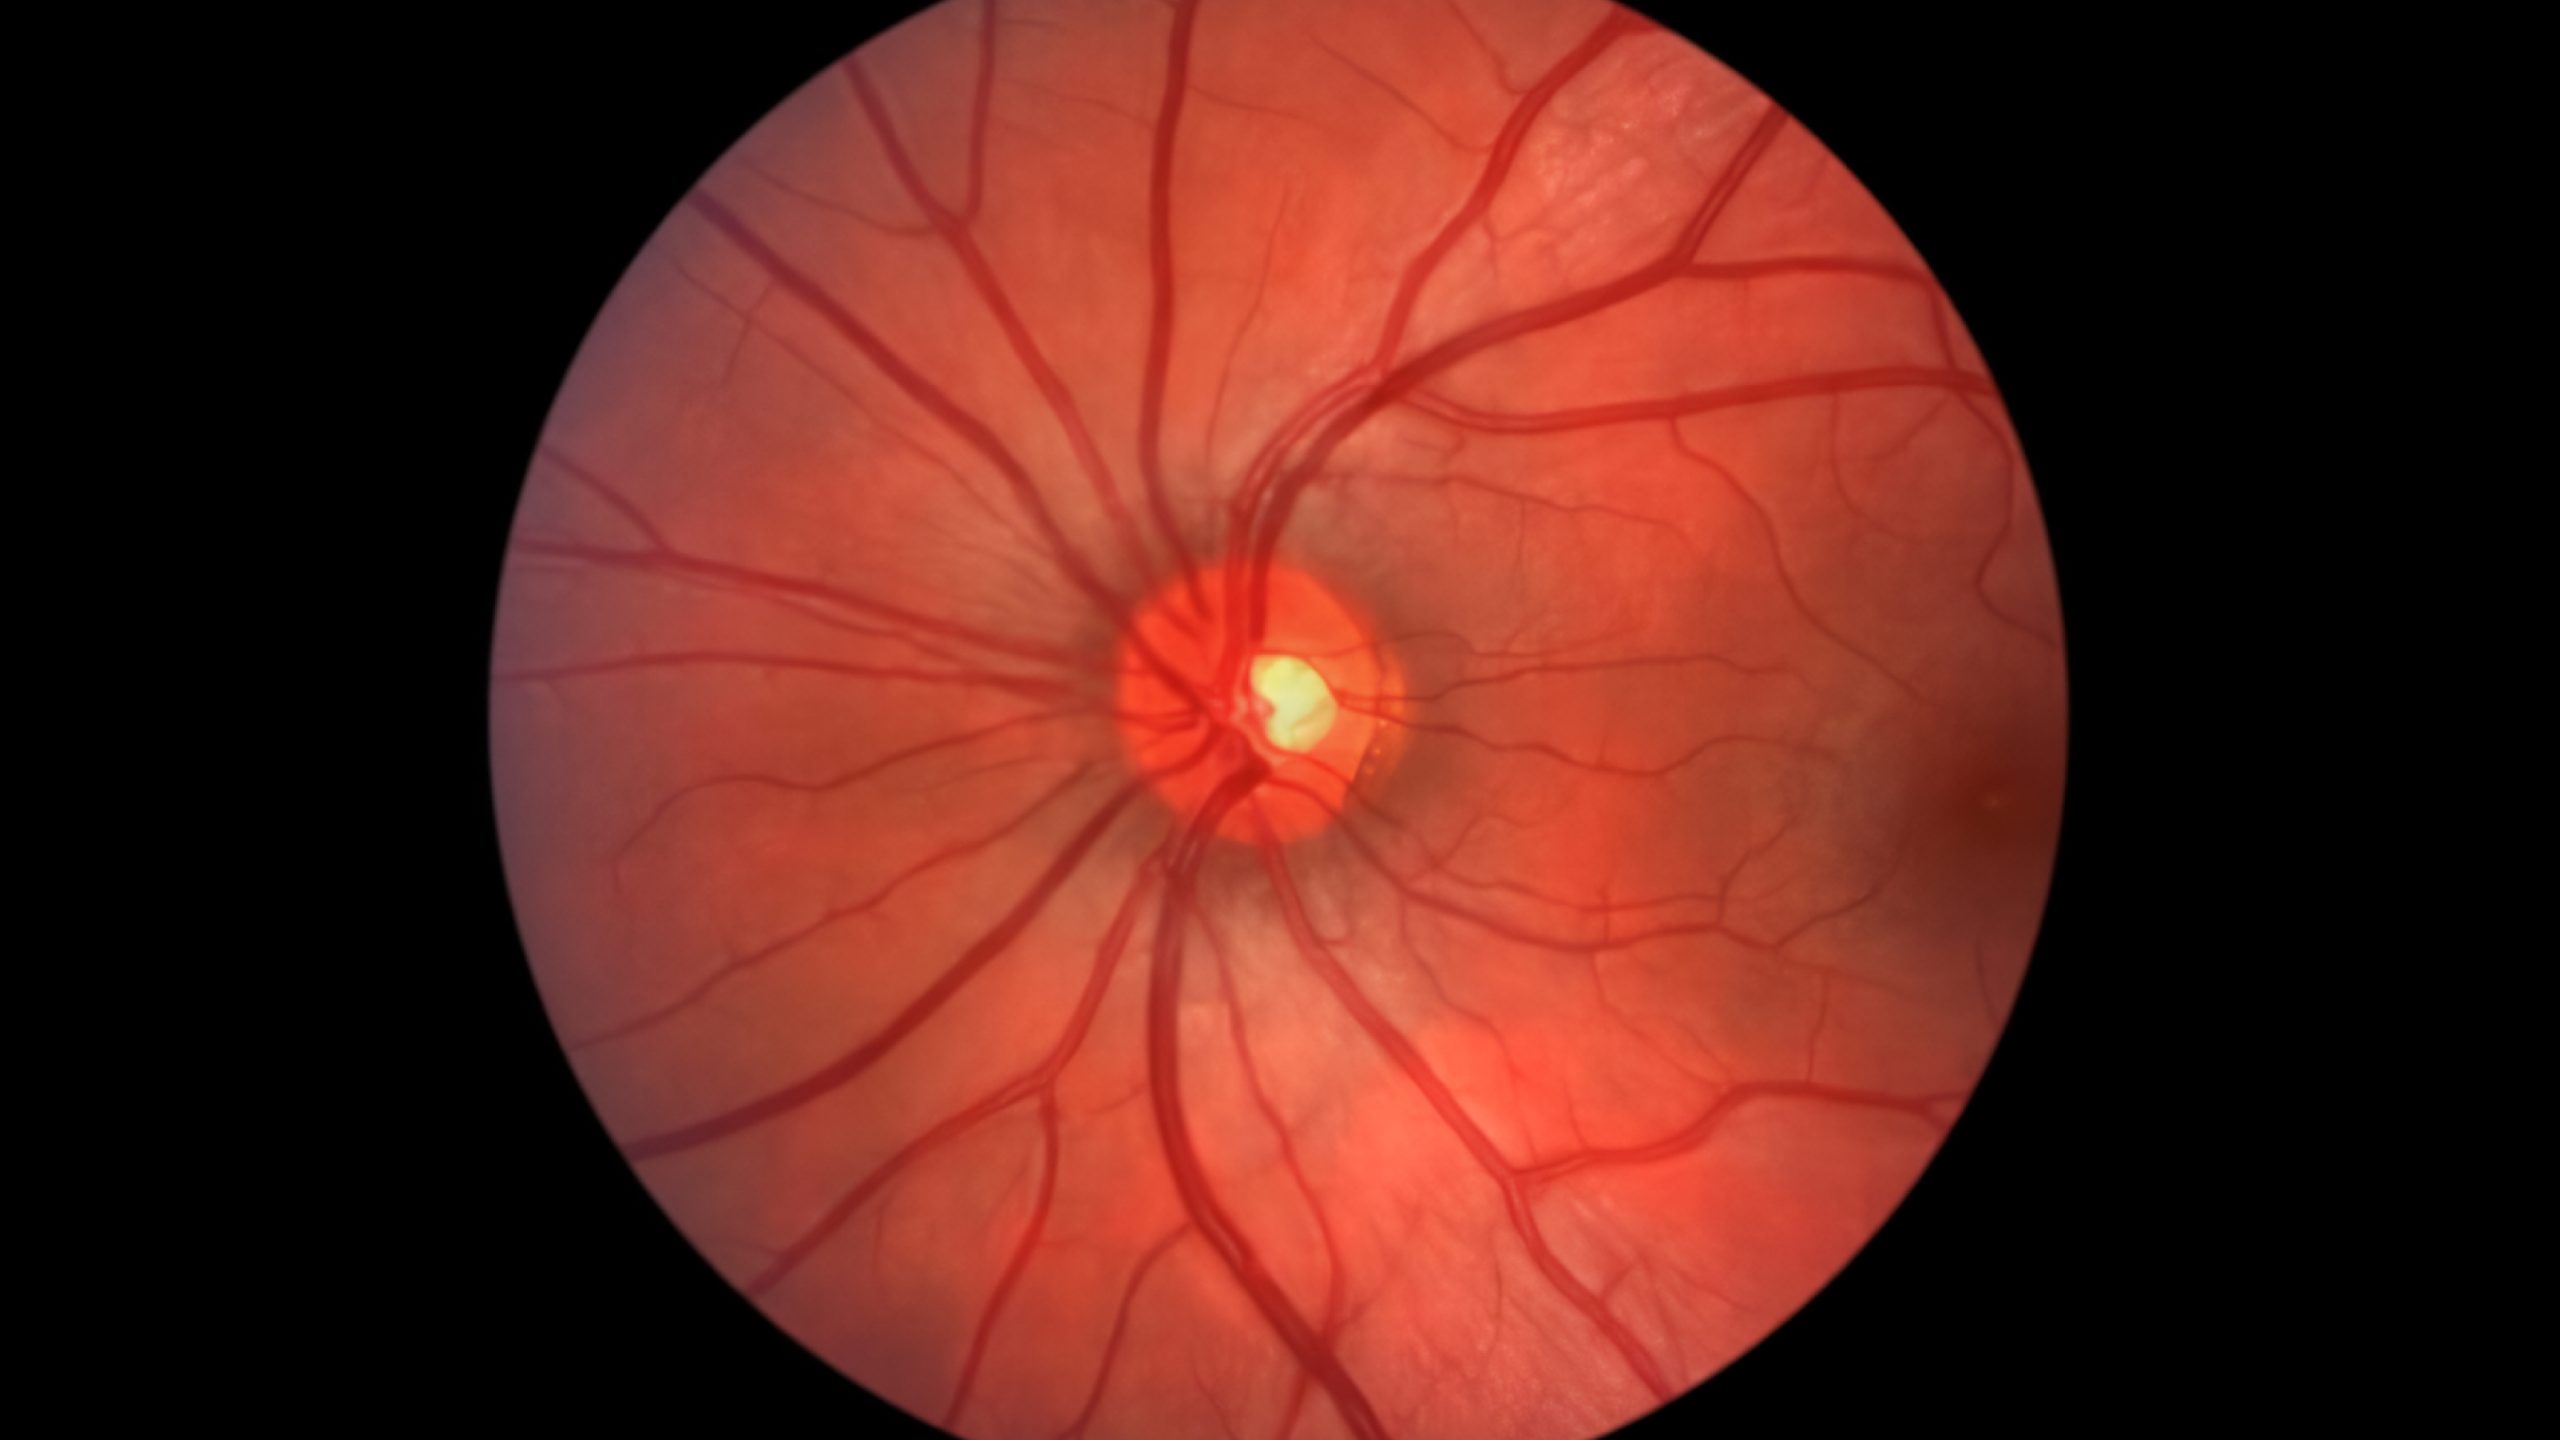

- 视网膜检查 (眼底照相):拍摄照片以观察您的眼后部,包括视网膜、视神经、黄斑和眼部血管,有助于检测青光眼、黄斑变性和糖尿病视网膜病变等疾病